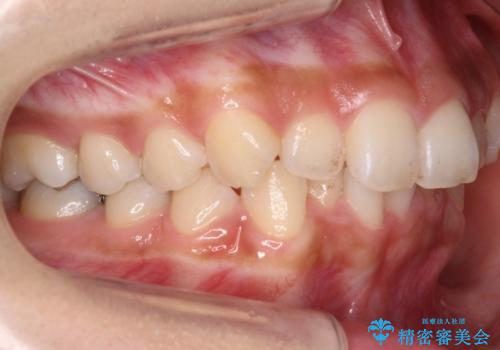

犬歯のねじれ 下の歯のがたがた インビザラインで

- 右上の犬歯のねじれ、下の歯のがたつきを主訴に来院。

インビザラインで歯を抜かずに並べました。